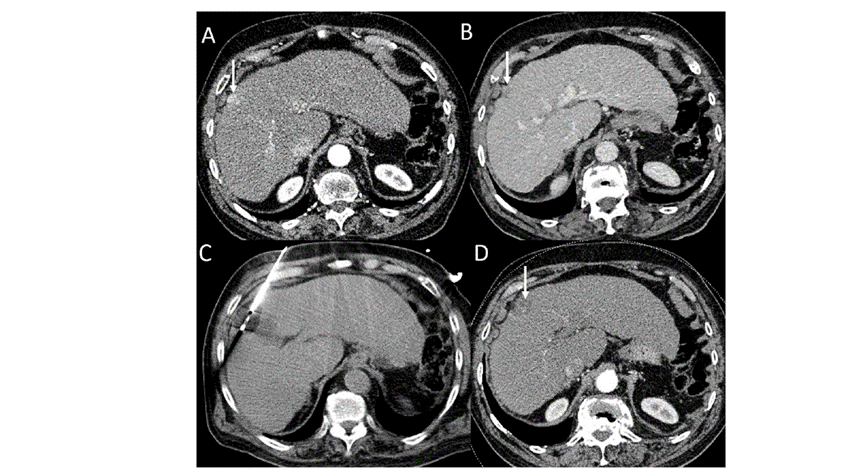

(A)动脉期CT图像显示有一个包膜下结节(箭头)。(C) 在手术过程中的CT显示一个冷冻探针位于病灶内。随访时间中位数为7个月(范围:3-12个月),随访期间患者无局部肿瘤进展或死亡。

(A)门静脉期 CT 图像显示胆囊附近有病变(箭头)。(D)消融手术后 1 个月CT 显示完全消融。

本研究中患者随访期间无局部肿瘤进展,无死亡病例,没有发现与手术相关的并发症。证实冷冻消融是一种有效的治疗方式,在技术上是可行和安全的。由于肝包膜下病变位置特殊,射频消融有出血及肿瘤种植的风险,可能会对邻近器官造成损伤,并且增加局部肿瘤进展的风险。近年来,冷冻消融术的应用逐渐广泛,有研究显示冷冻消融治疗具有明显优势,可治疗特殊部位的肝肿瘤。本研究的目的是评价冷冻消融治疗肝包膜下肿瘤的安全性和有效性。回顾性纳入2016年7月1日至2018年9月1日期间冷冻消融的57例患者。包括42例男性和15例女性,平均年龄为62.4岁(范围:48-82岁)。每个患者有1个或2个平均肿瘤尺寸为2.4cm的病变(范围:0.6-4.0cm)。所有患者均患有慢性肝病或肝硬化,并伴有乙型肝炎(n=52)、丙型肝炎(n=3)和其他肝炎(n=2)。根据肿瘤位置,在膈肌或肝脏下附近有18个病变(26.5%),胃或肠附近有9个病变(13.2%),腹壁附近有33个病变(48.5%),肾脏附近有8个病变(11.8%)。